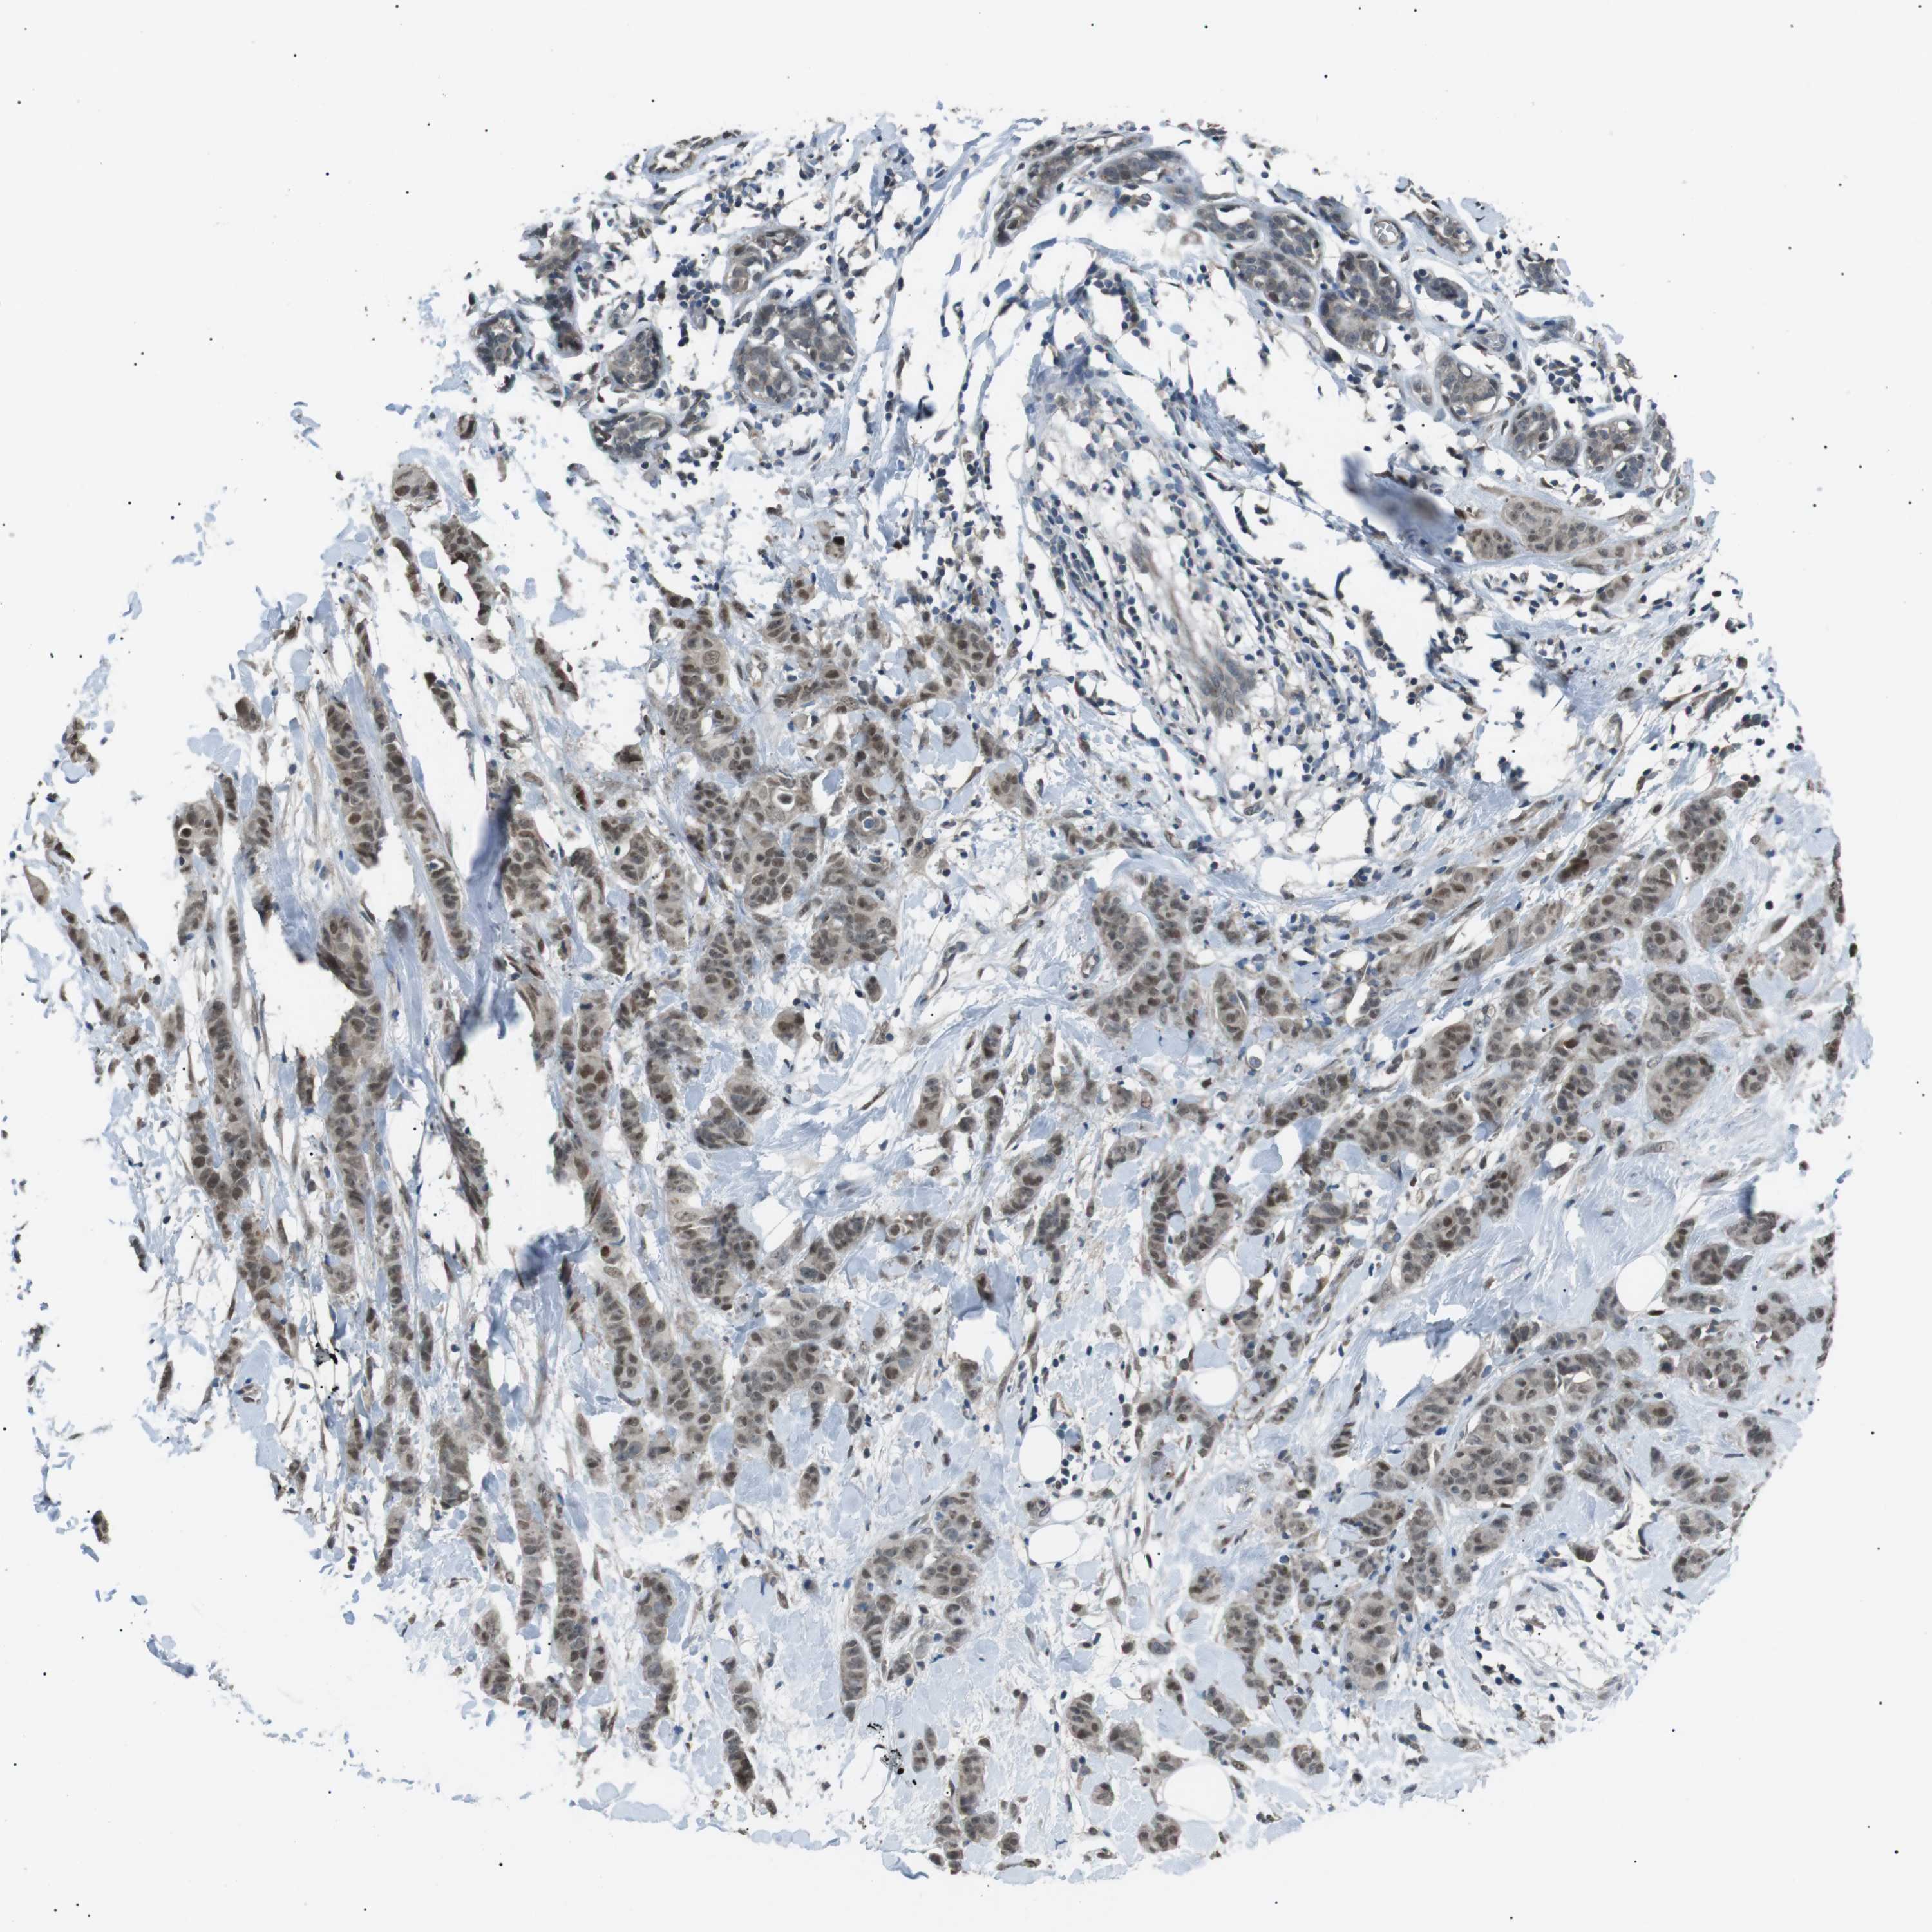

BRCA TCGA BRCA VALIDATION PROTEIN EXPRESSION